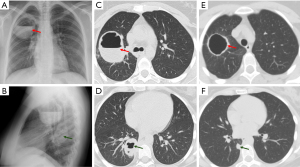

Septic emboli

Septic emboli occur when certain microorganisms cause peripheral pulmonary thrombosis, leading to infarction and microabscesses (7). Major risk factors for septic emboli include immunosuppression, the presence of arterial or intravenous catheters, intravenous drug use, alcoholism, endocarditis, and dental surgery (7,16).

Imaging findings of septic emboli include multiple subpleural, wedge-shaped nodules, which progress into cavities within days (Figure 6) (16). Cavitation is observed in up to 47% of cases on chest X-ray and up to 85% on CT (8). The “feeding vessel” sign, which indicates a distinct vessel leading to the center of the pulmonary nodule, is suggestive of septic emboli (8). Pleural effusion, hilar lymphadenopathy, and mediastinal lymphadenopathy may also be seen (8). The rapid progression of nodules to cavities helps to differentiate them from malignancies (8).